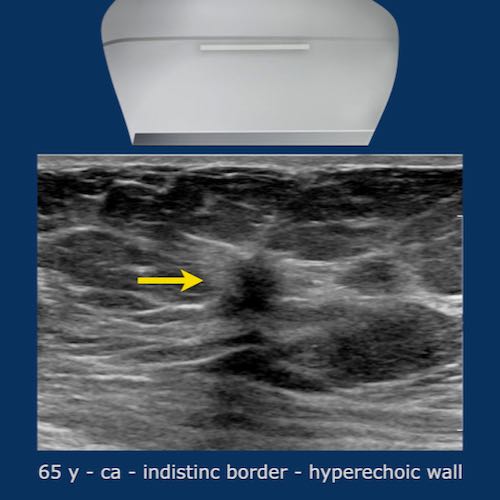

Quầng tăng âm (Hyperechoic halo)

Một dấu hiệu thường gặp trong ung thư vú là quầng tăng âm bao quanh khối giảm âm.

Quầng này là một phần của khối u và cần được tính vào kích thước đo của khối u.